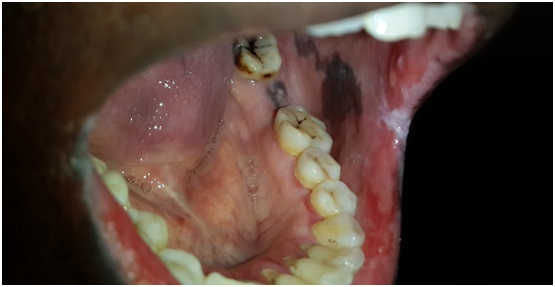

Clinical examinations: Tender diffuse irregular shallow bloody ulcers affected the lower lip and bilateral buccal mucosa and oral commissures. Also bilaterally a racial pigementations were appeared on buccal mucosa (Figures 1-3). There were no detectable cutaneous target like lesions and no palpable submandibular or cervical lymphadenopathy.

Figure 1 shows a diffuse irregular shallow bloody ulcers in the lower lip.

Figure 2 Shows diffuse irregular bloody ulceration in the right buccal mucosa.